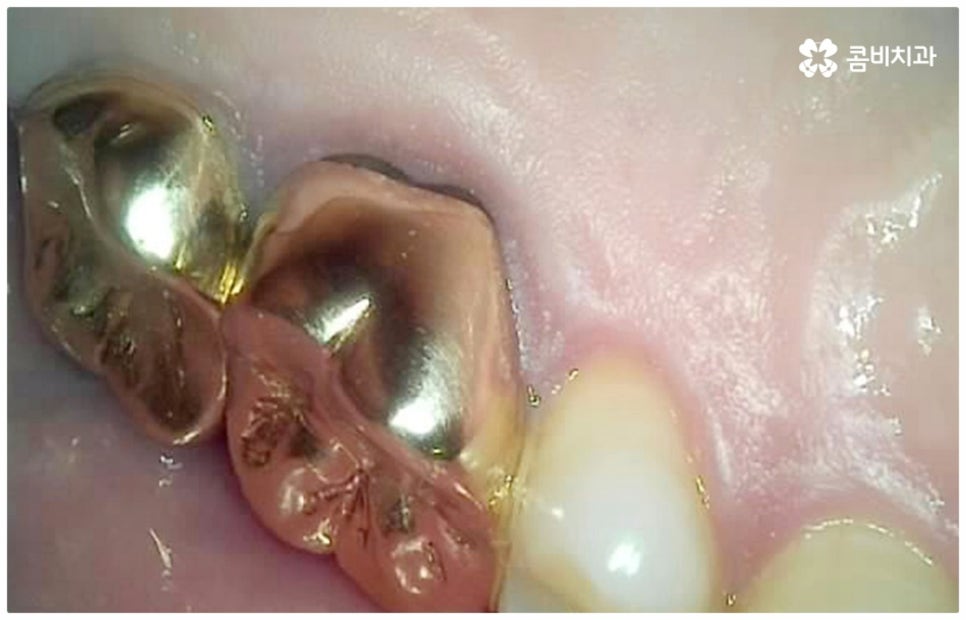

그러나 요즘 임플란트 관련 기술이 많이 발달하여 자연 치아 상실에 대처하는 가장 대표적인 인공 치아 시술로 손꼽히고 있다고 해도 구조적인 차이점으로 인해 타고난 치아와 똑같을 수는 없다는 점, 자칫 관리에 소홀하면 잇몸 질환에 취약하여 주변 치아까지 좋지 않은 영향을 받을 수도 있다는 점 등을 고려해 봤을 때 구강 건강을 위해서는 될 수 있는대로 자연 치아의 수명을 늘리는 것이 보다 의미가 있습니다.

사실상 신경치료나 재신경치료가 어금니충치치료 중 거의 마지막 단계의 보존 치료에 속하는 것임을 감안해 봤을 때 해당 치료를 받은 자연 치아의 수명이 얼마나 될까 궁금해 하시는 분들도 있는데요. 환자분들의 상황에 따라 다르지만 신경 치료를 한 치아의 평균 수명은 약 11년 정도 (후속 처치인 크라운 치료를 함께 받았을 경우 약 20년까지 수명이 늘어남) 라는 연구 결과가 있는 만큼 치료 시기를 놓치지 않도록 주의를 기울이고 관리하면서 필요하다면 바로 뛰어난 노하우를 가지고 있는 숙련된 의료진에게 꼼꼼하게 신경 치료를 받을 수 있도록 하는 것이 중요한 포인트라고 할 수 있어요.